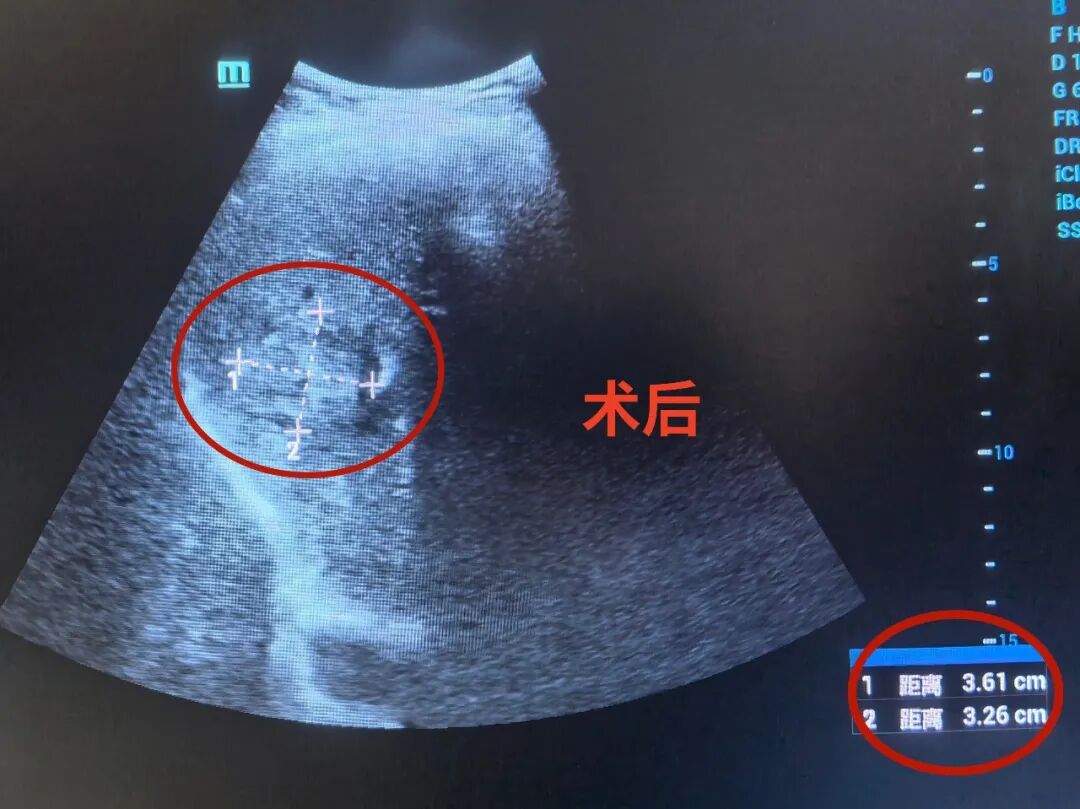

术后,综合内科团队给予对症治疗,不久黄阿姨的症状便明显改善,精神状态也日渐好转。 复查彩超显示,肝脓肿已明显缩小。 “现在感觉舒服多了,整个人都轻松了,真的太感谢陈主任、石主任和医护团队了!”黄阿姨感激之情溢于言表。